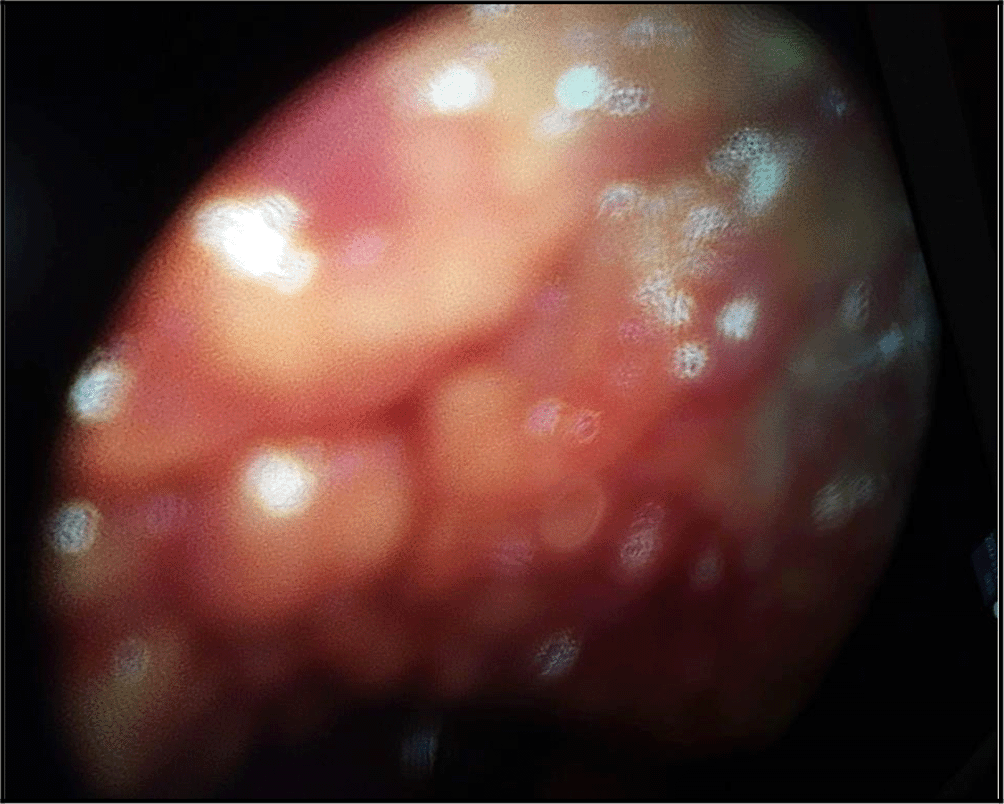

A medical thoracoscopy was performed 9 days after her admission in our department. It showed a multinodular pleura with a “bunch of grapes” sign (Figure 4). It allowed guided pleural biopsies as well as chemical pleurodesis in order to prevent the pleural effusion recurrence.

The diagnosis was very challenging. In fact, we initially suspected an advanced stage lung carcinoma giving the chest CT scan’s findings, or a mesothelioma due to the multinodular aspect of the pleura in the chest ultrasound and “the grape-cluster” appearance as seen in thoracoscopy. Histology helped us to assess the right diagnosis.

The diagnosis requires the presence of a monoclonal protein or a light chain in the pleural fluid, abnormal plasma cells with an intense staining CD138.13–16 Medical thoracoscopy is actually recommended in the case of such malignant pleural effusion. In fact, it allows pleural guided-biopsy with a good-quality sampling, pleural fluid drainage as well as pleurodesis in order to prevent the recurrences during the follow-up.8,17,18 In our case, medical thoracoscopy showed a multinodular pleura with “a buck of grapes” like aspect. We decided to perform chemical pleurodesis given that most of the reported cases had a high rate of recurrence of the pleural effusion. Flow cytometry may be a useful tool to assess the diagnosis.19